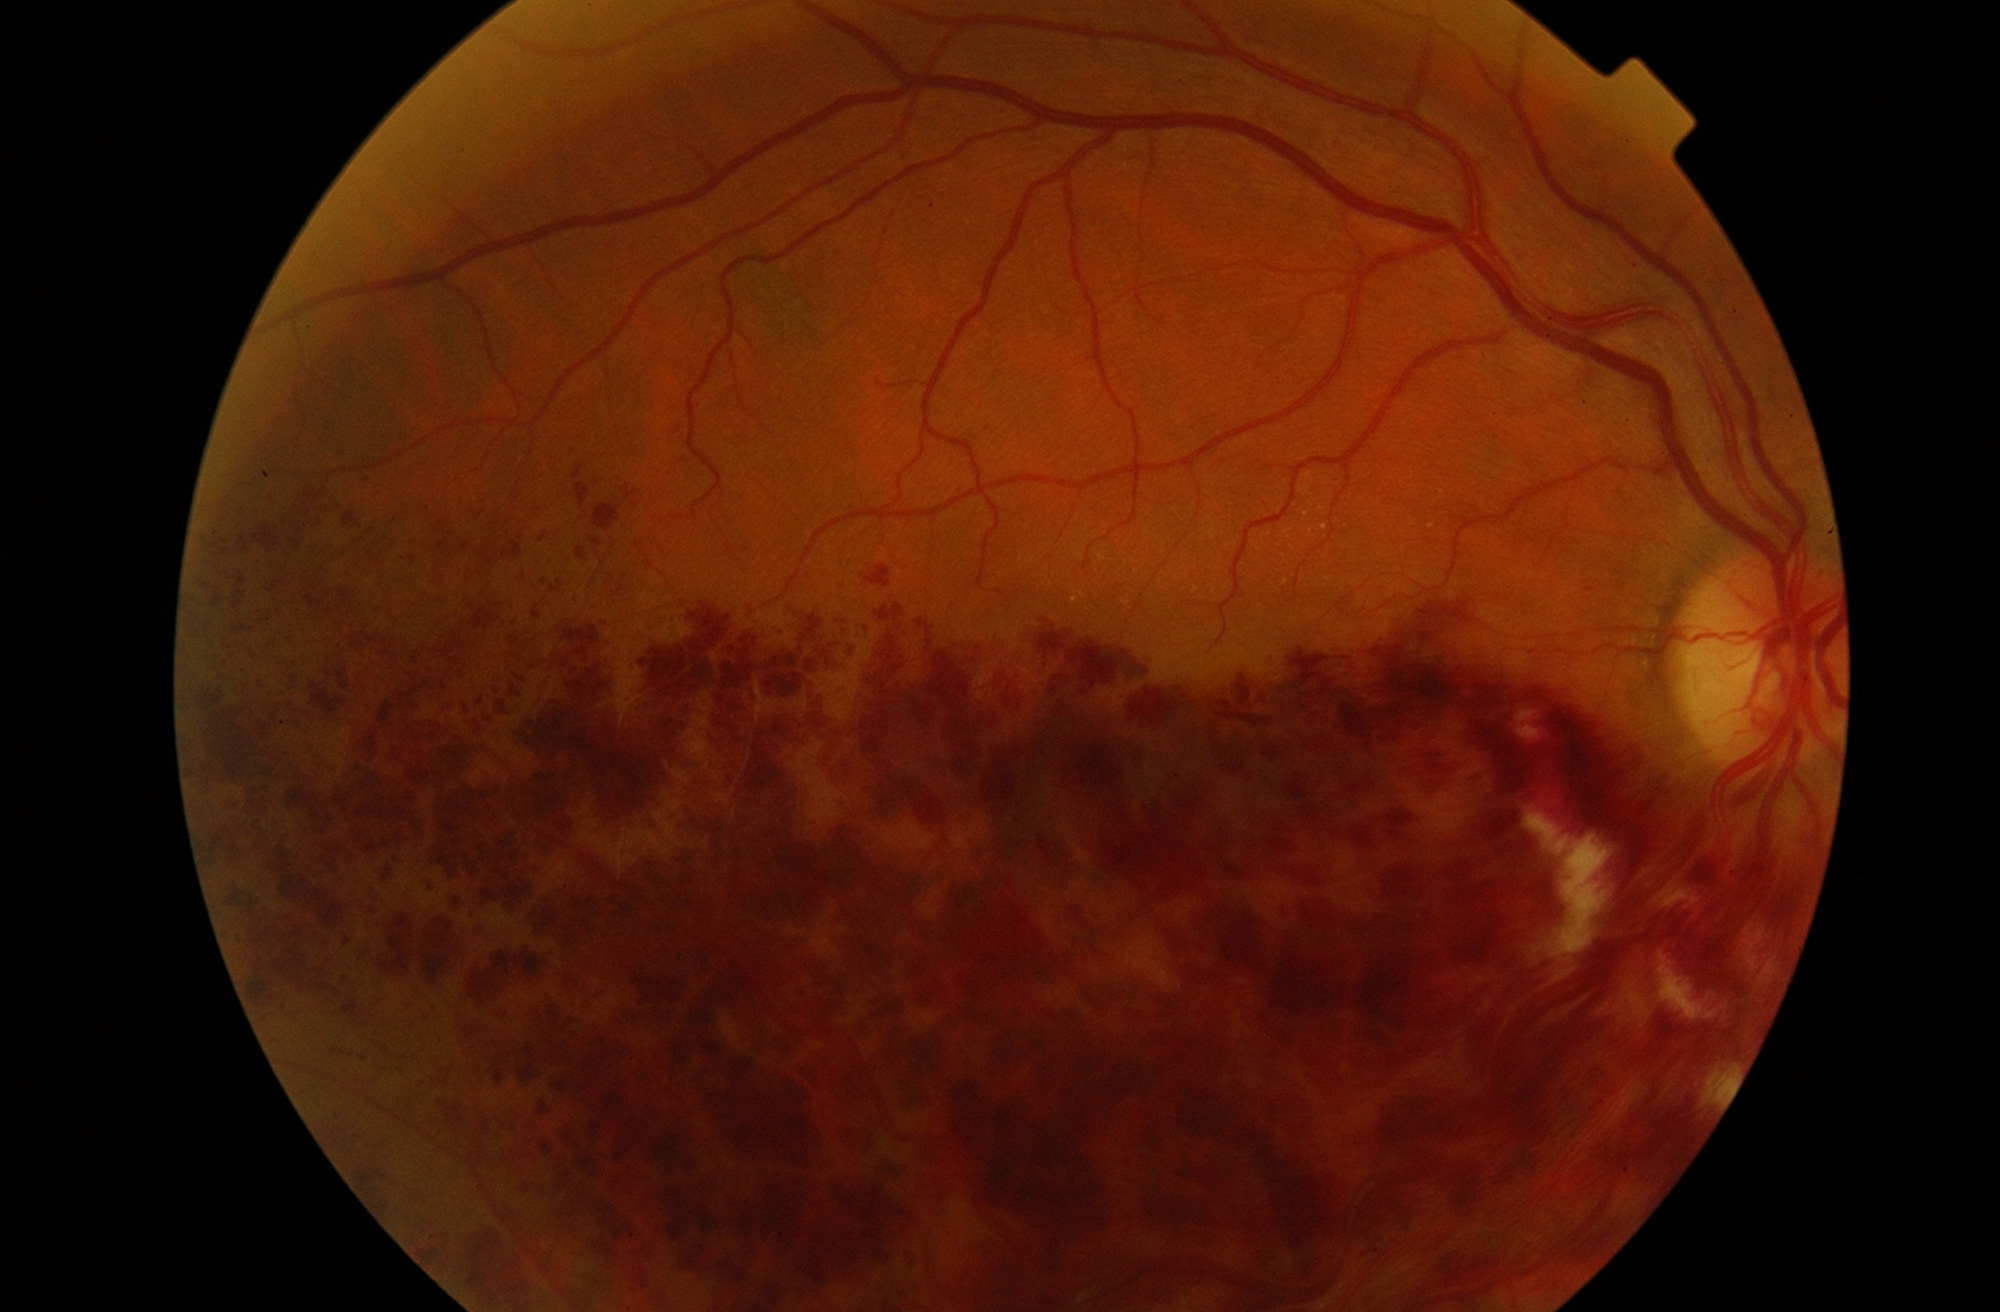

Hemorragia intraocular

Son varias las enfermedades que pueden dar un sangrado intraocular. Las más frecuentes son la retinopatía diabética, el desgarro retiniano, la degeneración macular asociada a la edad o un traumatismo ocular.